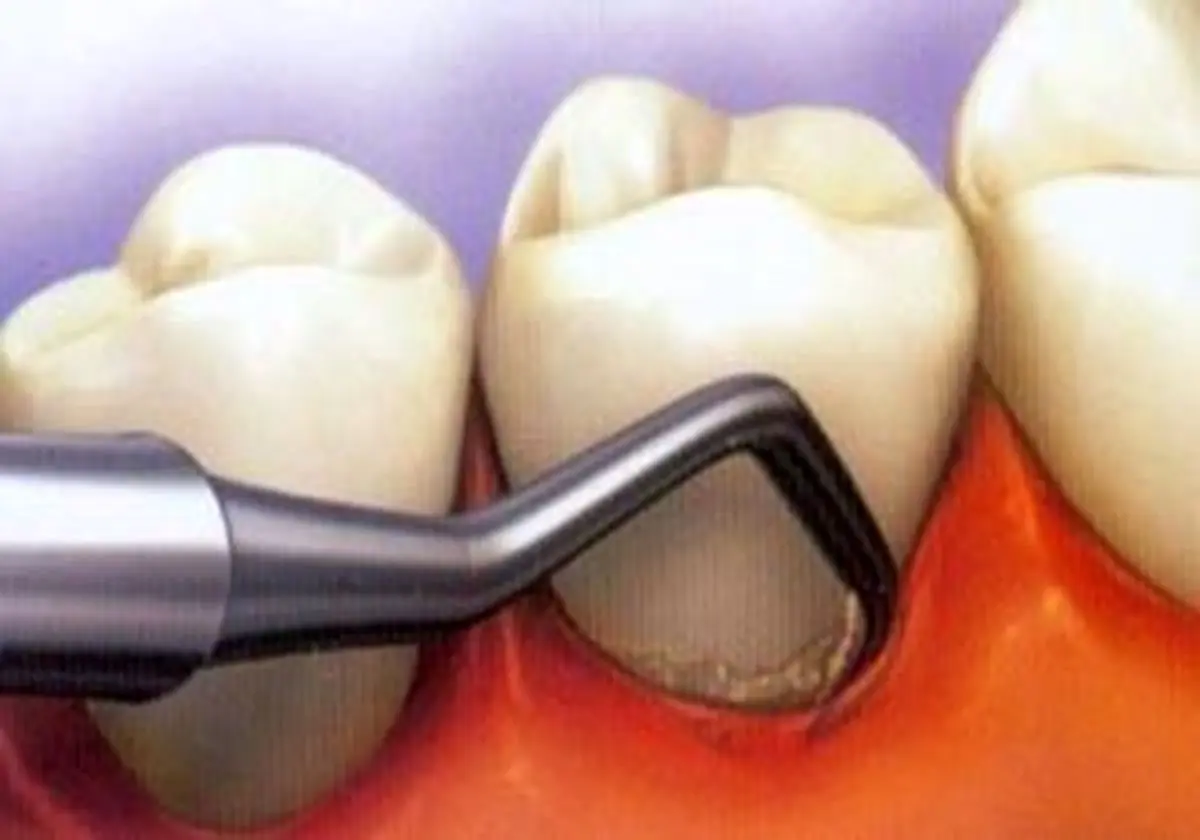

جرم گیری برای دندانها مضر است؟

دکتر عبدالحمید ظفرمند دندان پزشک و عضو هیئت علمی دانشگاه علوم پزشکی شهید بهشتی در خصوص زمان جرمگیری دندان گفت: در صورتی که بهداشت دهان و دندان رعایت نشود به مرور غذاها و یا پلاکهای سرخی که روی دندان قابلیت تمیز شدن را دارند سخت میشوند و در این هنگام دیگر وسایل معمولی مثل نخ دندان و یا مسواک قابلیت بر طرف کردن آنها را ندارد. به همین خاطر لازم است با وسایل حرفهایتر اجسامی را که به دندانها چسبیدهاند را برداشت که اگر به موقع انجام نشود سلامت لثه را تهدید خواهد کرد.

وی ادامه داد: بروز التهاب در لثهها و همچنین تحلیل رفتن استخوان فک از جمله خطراتی است که سلامت دهان و دندان را تهدید خواهند کرد.

ظفرمند اظهار کرد: وقتی میزان جرمهای دندان در حدی باشند که به استخوان نگهدارنده دندان در داخل فک و لثه صدمه وارد کند به احتمال قوی به درمانهای پیشرفته نیاز خواهد داشت.

وی خاطر نشان کرد: حساسیتی که پس از جرمگیری بروز مییابد ارتباط و مشکلی با برداشتن جرم ندارد، اما در هر صورت بنابر تشخیص پزشک درمان صورت میگیرد چرا که برای رفع حساسیت میتوان از خمیر دندانهای ضد حساسیت استفاده کرد و در موارد شدیدتر استفاده از دهانشویه حاوی فلوراید منعی ندارد.